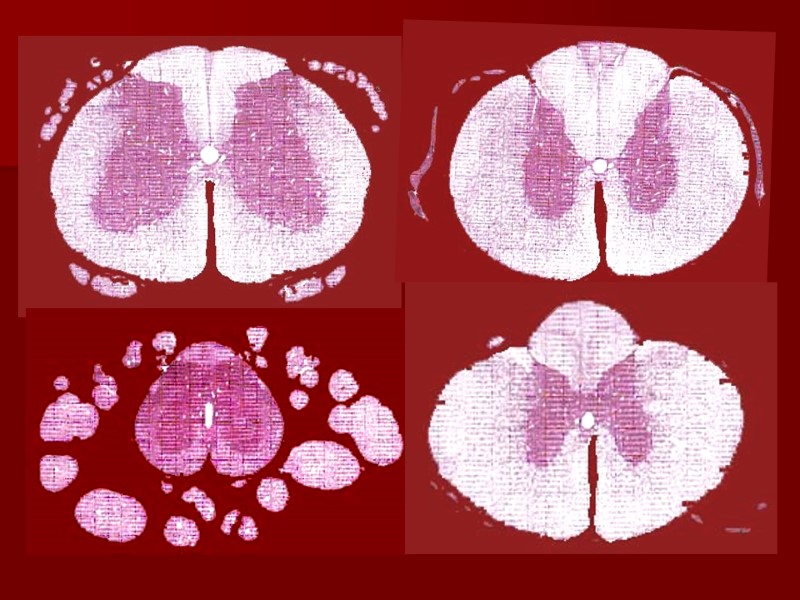

Белое вещество содержит преимущественно миелиновые нервные волокна, однако безмиелиновые волокна также в нем присутствуют и поддерживают аксоны и дендриты, бегущие вверх и вниз по спинному мозгу. Раздел между серым и белым веществом в спинном мозге очевиден. H&E, x132 Серое вещество содержит тела нейронов, много безмиелиновых волокон, небольшое количество миелиновых нервных волокон и массу клеток глии, CB BV W

Спинной мозг (шейный отдел) H&E Белое вещество расположено по периферии спинного мозга, а серое – в центре, образуя картину бабочки.

Мозжечок, серебрение В головном мозге имеет место обратное соотношение серого и белого вещества, где белое вещество (мозговое) располагается глубоко под корой (серым веществом).